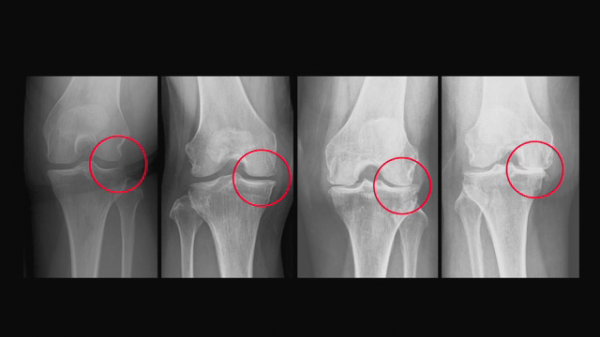

6일 방송되는 EBS '명의-무릎 골관절염'에서는 당신이 진짜로 궁금한 무릎 골관절염의 해답을 알아본다.

전체 환자 중 50대 이상 환자가 무려 90%를 차지한 중년과 노년의 삶을 위협하는 대표적인 질환으로 떠오른 무릎 골관절염. 주변에서 한 번씩은 ’무릎이 아프다‘ , ’인공관절 수술을 받았다‘라는 얘기를 들어 볼 수 있을 정도로 많은 사람이 앓고 있는 병이다. 인공관절 수술 건수는 매년 증가해 작년에는 무려 11만 건을 넘어섰다.